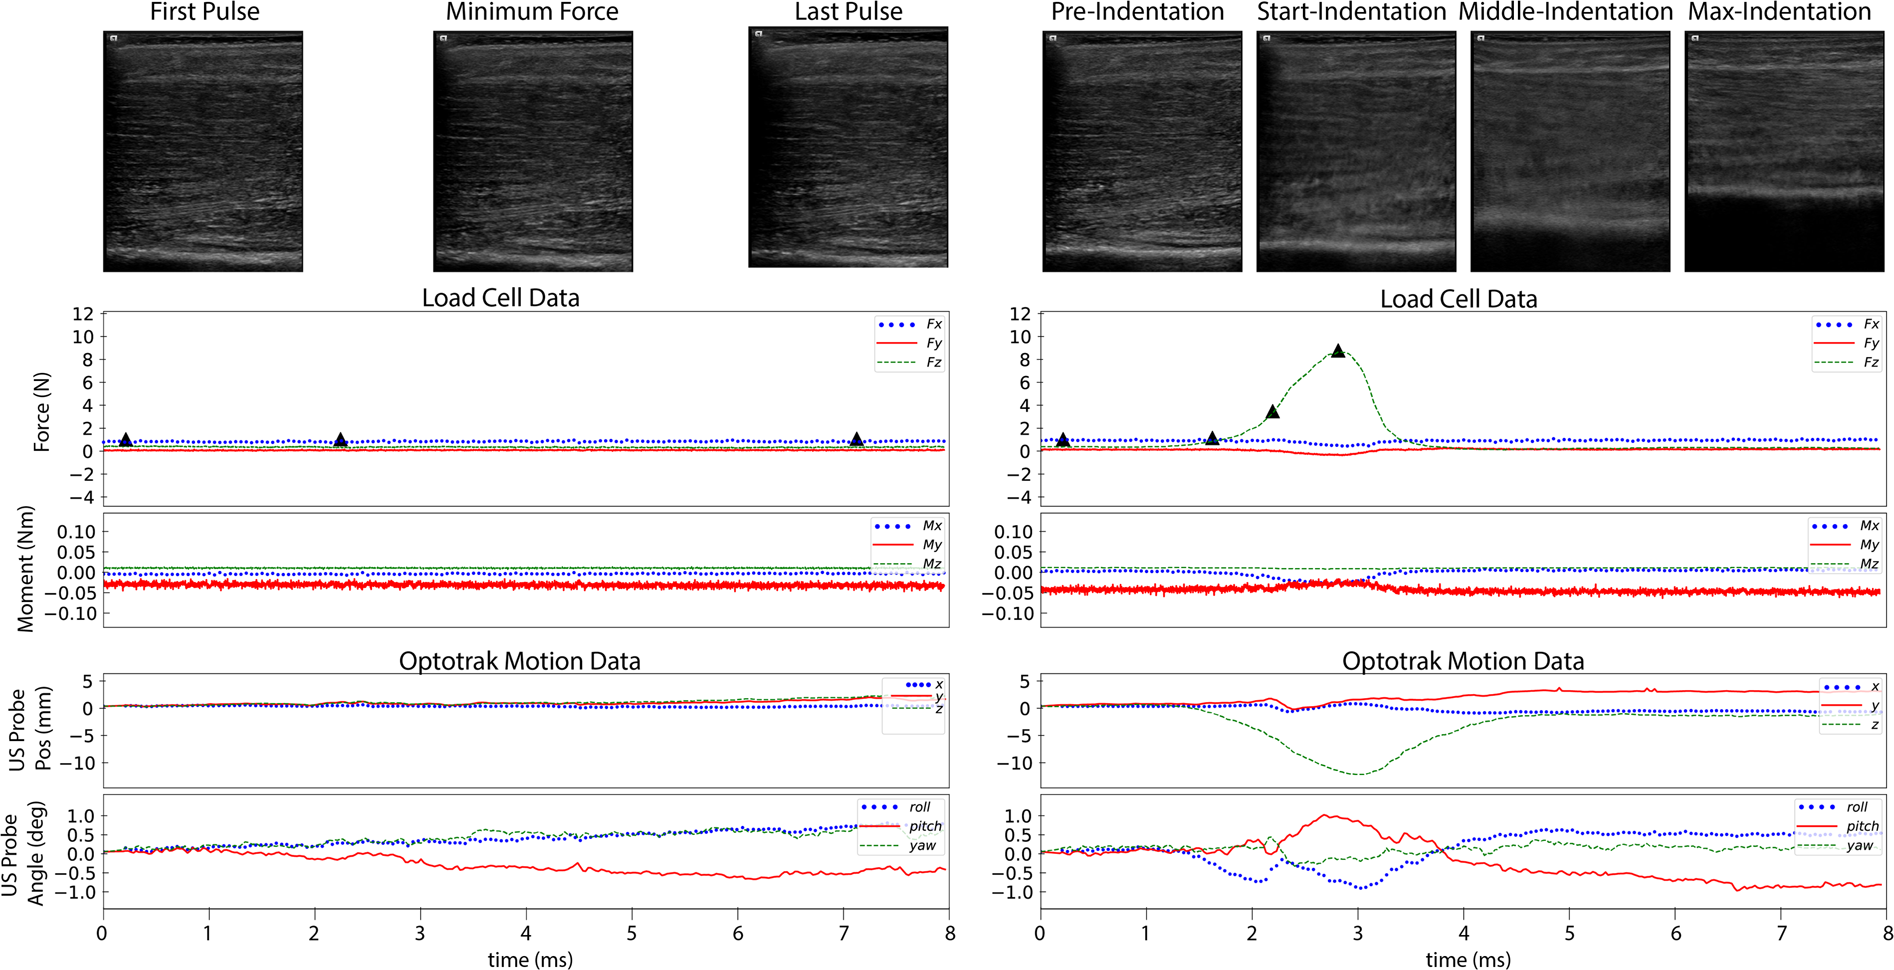

Fig. 4

Sample load and motion data. The left panel shows an anatomical trial (032_CMULTIS012-1_UL_PC_A-1) and the right panel shows an indentation trial (033_CMULTIS012-1_UL_PC_I-1). From top to bottom are ultrasound images, forces, moments, and motion of ultrasound probe (position and angle). The forces and moments were reported in a probe tip coordinate system originating on the center face of the ultrasound probe (the Z-axis is aligned perpendicular to the face and in the direction of applied load). The motion was reported in global motion capture coordinate system. The triangle shapes on the force plot represent the time instance in which the respective ultrasound image was taken.